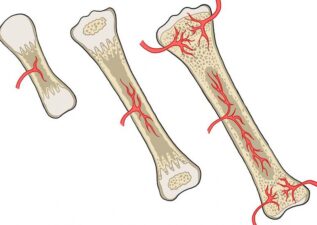

ورود رگهای خونی و آغاز سختشدن

تحول اصلی زمانی رخ میدهد که رگهای خونی به این مدل غضروفی نفوذ میکنند. با ورود خون، اکسیژن و مواد غذایی، سلولهای خاصی بیدار میشوند و عملیات تبدیل غضروف به استخوان آغاز میگردد:

مرکز اولیه استخوانسازی: در وسط استخوان (دیافیز) شکل میگیرد.

مرکز ثانویه استخوانسازی: بعدها در دو سر استخوان (اپیفیز) ایجاد میشود.